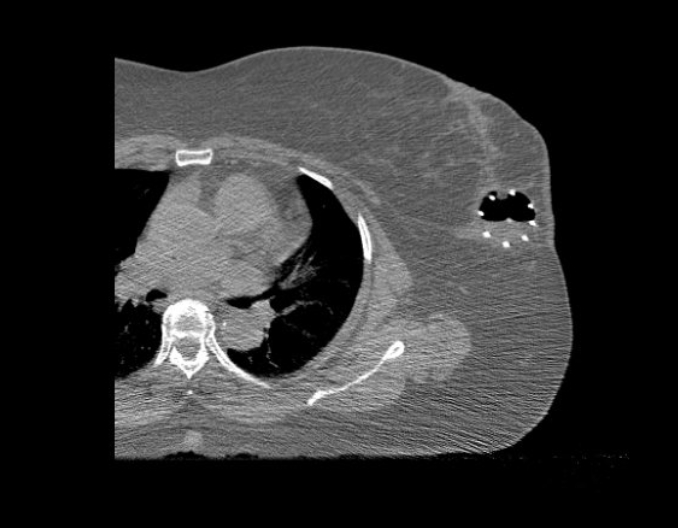

Brachytherapy Image Gallery